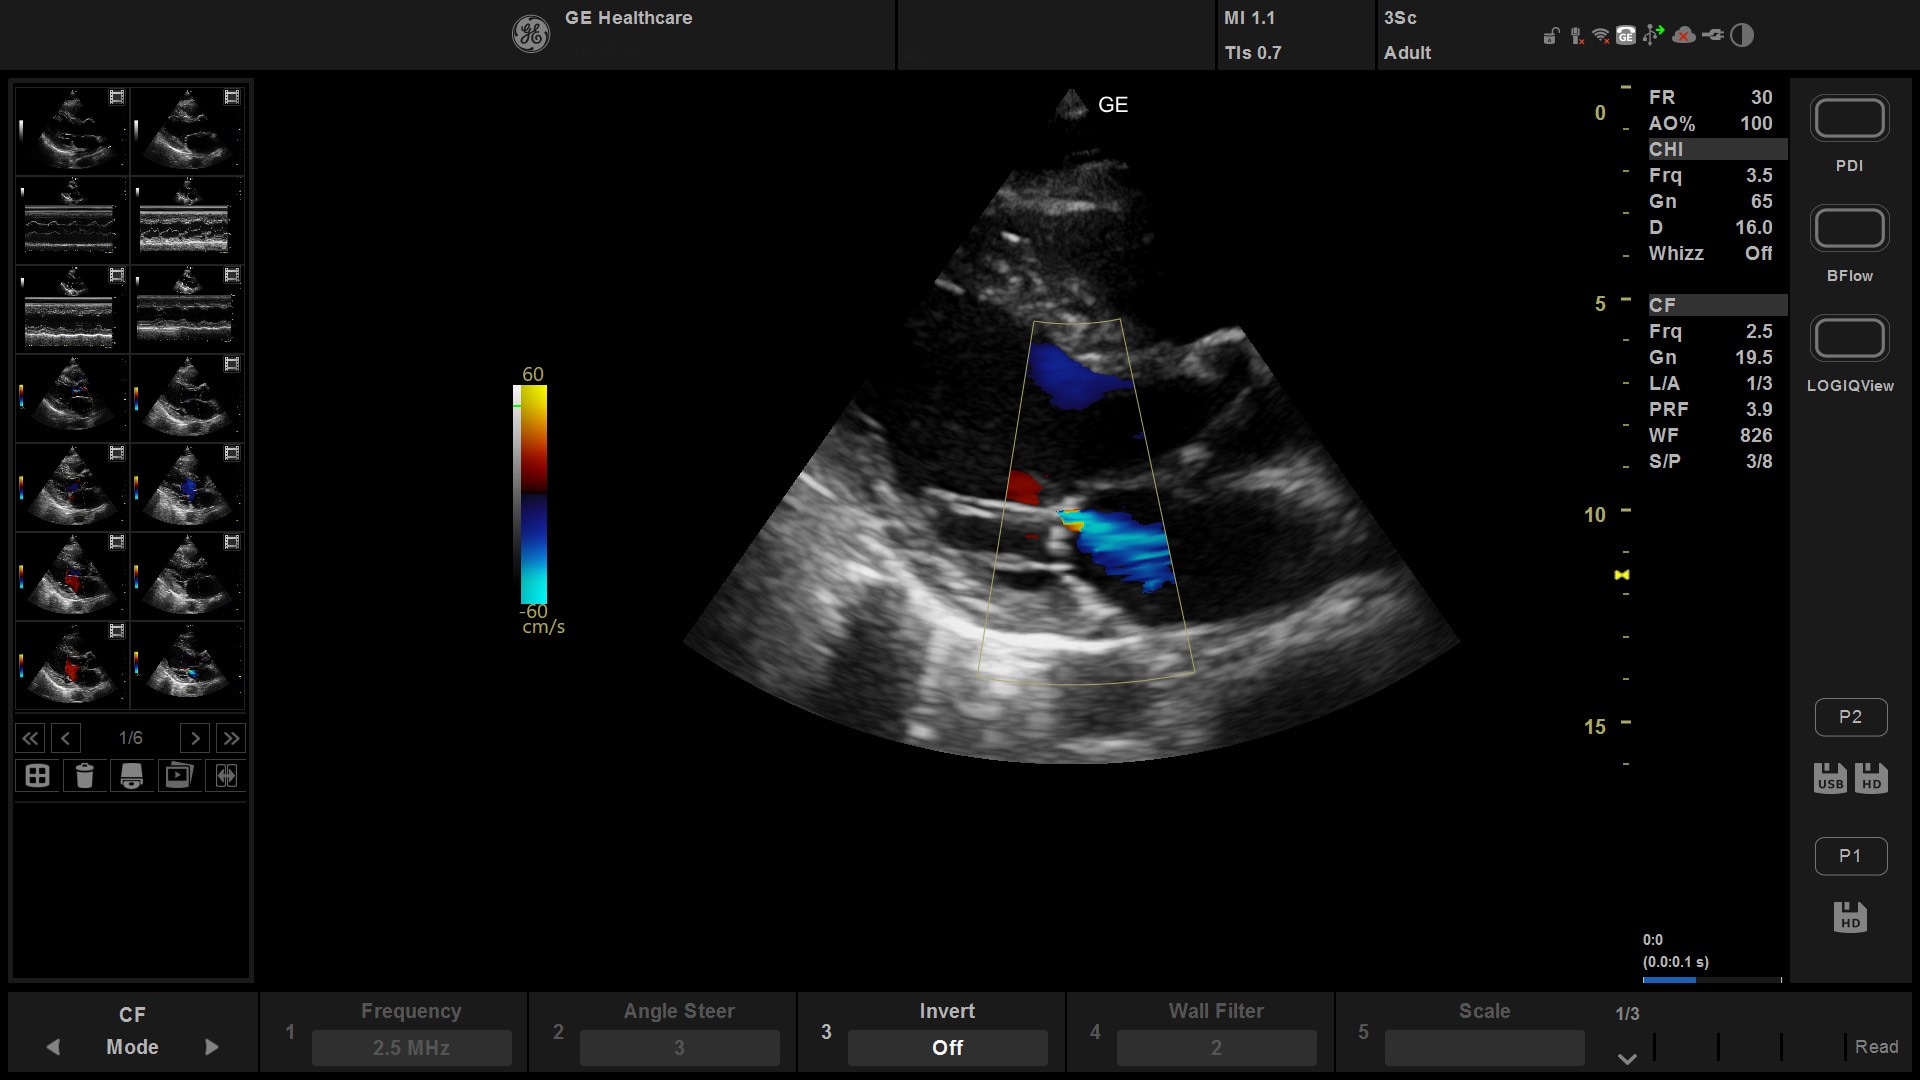

Suited for abdominal, small parts, cardiac, OB/GYN, vascular, and MSK exams

Versana Active features a wide range of advanced clinical applications and automated tools that simplify exams, streamline workflow, and enable fast, high-volume scanning to help you diagnose a wide spectrum of patient conditions.